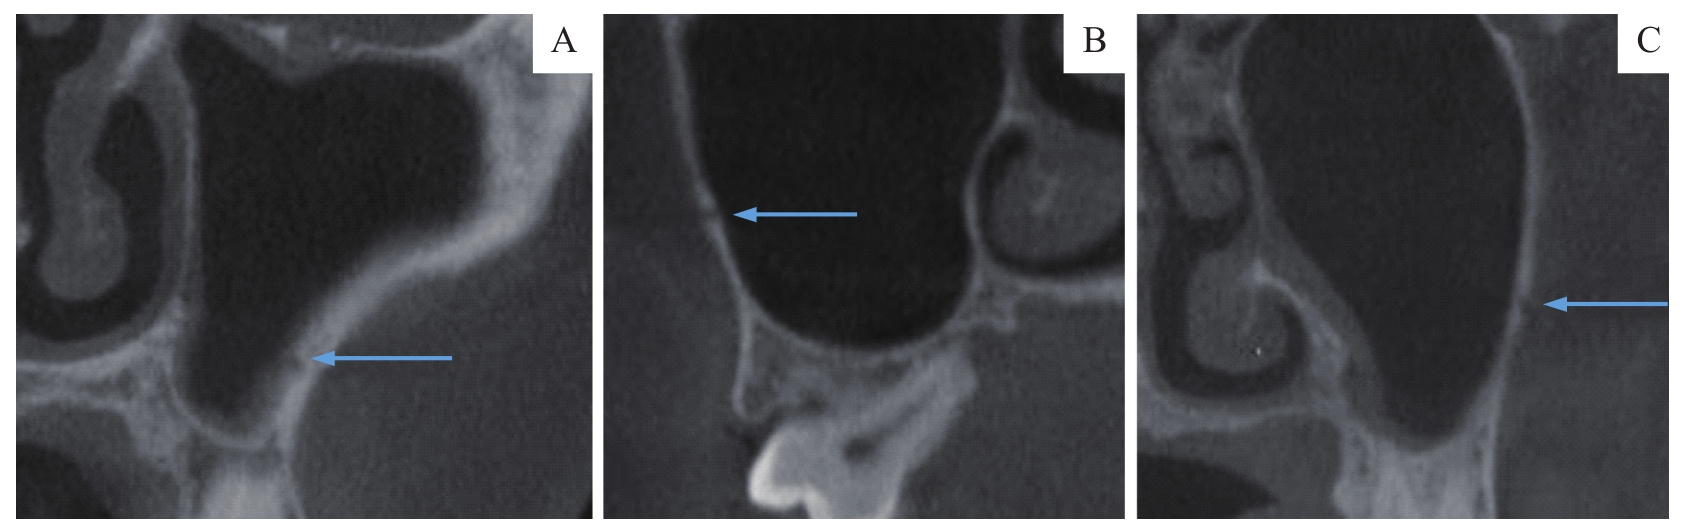

| 图1 MSA走形类型 Note:A. Intrasinus type. B. Intraosseous type. C. Superficial type. |

| Fig 1 Shape type of MSA |